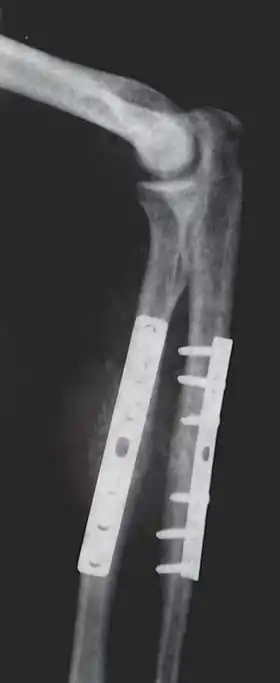

Orthopaedic implants help alleviate issues with the bones and joints of the body.[7] They are used to treat bone fractures, osteoarthritis, scoliosis, spinal stenosis, and chronic pain. Examples include a wide variety of pins, rods, screws, and plates used to anchor fractured bones while they heal.[3][5][6]